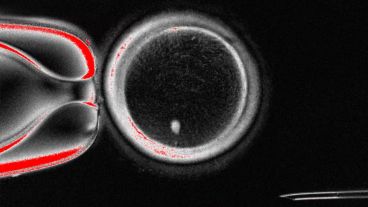

Desde la OHSU (Oregon Health & Science University) de Estados Unidos, se desarrolló una técnica experimental denominada mitomeiosis. El procedimiento consta de transferir el núcleo de una célula somática (como las de la piel) a un óvulo donado sin núcleo, provocando que divida su carga genética (como sucede en la meiosis natural).

Con este experimento se obtuvieron 82 óvulos funcionales que fueron fecundados con esperma humano. Un 9% alcanzó la fase de blastocito, correspondiente a los primeros seis días de desarrollo embrionario. Si bien ninguno se cultivó más allá de ese punto, para los autores se trata de una prueba de concepto que demuestra la viabilidad de generar gametos humanos por medio de células somáticas.